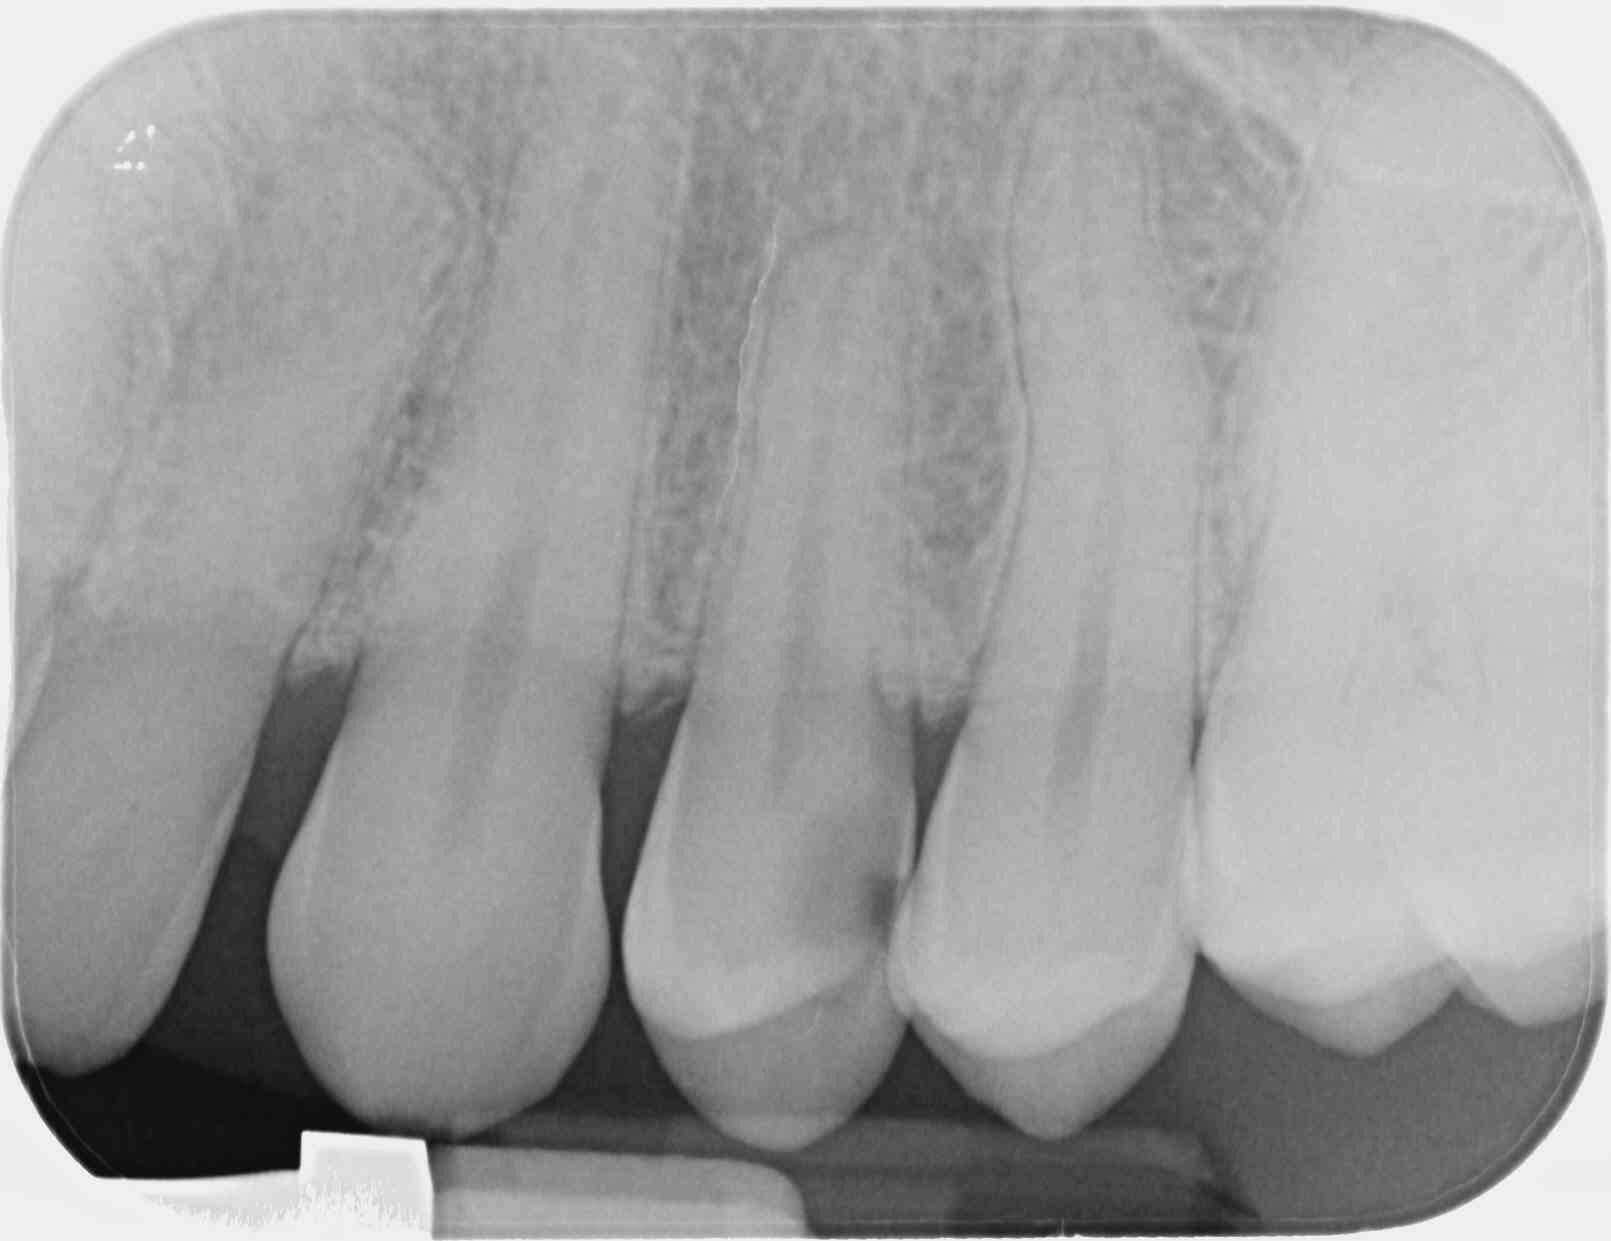

Tiens, une belle nécrose palatine suite à l'endo de cette 24 il y a 15 jours.

Vu la rvg pré-op, je ne pensais pas avoir de difficulté à réaliser une ostéocentrale : j'ai mis 3/4 de carpule à 1/100000 en mésial avec plus de difficulté et moins d'efficacité qu'à l'accoutumée. Je devais être trop palatin. J'ai du compléter en distal, sans souci cette fois.

Question con: pourquoi l'endo? la carie semble pas si profonde....

- endo car dent symptomatique et j'ai écorné en curetant.